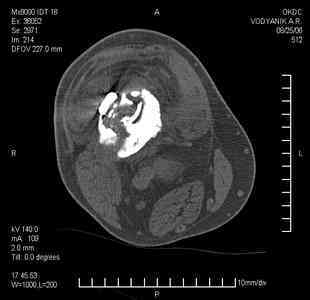

Тугой ложный сустав правого бедра в сочетании неправильно сросшимся переломом большеберцовой кости |

Уважаемые коллеги,В ортопедическое отделение обратился пациент: мужчина 47 лет, который в течение 4-х лет дваждыполучил травму костей, образующих правый коленный сустав. В 2002 v внутрисуставной оскольчатыйперелом проксимального метаэпифиза правой большеберцовой кости; в 2005 v внутрисуставнойоскольчатый перелом дистального метаэпифиза правой бедренной кости. В обоих случаях в разных лечебных учреждениях проводилось оперативное лечение переломов.При осмотре в отделении на основании результатов клинического осмотра и данных визуальныхметодов обследования поставлен диагноз:тугой ложный сустав дистальной трети правой бедренной кости, состояние после накостногоостеосинтеза перелома типа 33-В2.2 ; несросшийся перелом надколенника; неправильно сросшийсяперелом латерального мыщелка правой большеберцовой кости, состояние после металлоостеосинтезаперелома 41-В2.2; сочетанная осевая деформация правой ноги: варусная деформация правого бедра,вальгусная деформация правой голени; посттравматический артроз коленного сустава 4 ст по Kellgren-Lowrence; выраженное нарушение функции ходьбы и опоры. Внешний вид ноги больного, данные рентгенографического обследования и избирательно выделенные компьютерные томограммы приведены в приложении. В именах КТ использовано кодирование уровня по АО, т.е. _41, например, означает проксимальную треть голени.В отделении намечен v очень предварительно v следующий план лечения: 1. Иметь ввиду перспективу тотального эндопротезирования коленного сустава. 2. С учетом п.1 при проведении действий, направленных на устранение ложного сустава бедренной кости не использовать материалы, не подвергающиеся трансформации. 3. В ходе операции, направленной на устранение ложного сустава: А. удалить все металлоконструкции; Б. ревизовать зону пролежня под пластиной на бедре, при наличии признаков достаточной жизнеспособности кости выполнить остеопериостальную декортикацию, дрилинг ложа пластины; В. Удалить рубцовую ткань по плоскости ложного сустава, и в пространстве между костными форагментами, насечь обращенные друг к другу поверхности. Ввести штифт с блокированием (например Stryker с учетом особенностей расположения дистальных блокирующих винтов у этойконструкции). Осуществить остеосинтез с учтанением варусной деформации бедренной кости. Пространство в зоне ложного сустава и пустоты в метафизе бедренной кости заполнить резорбирующимся цементом на основе гидроксиапатита кальция. Для дистальной фиксации использовать винты с переменным шагом резьбы. Вариант:, винты вводить после заполнения метафиза цементом. Дополнительные виды создания межфрагментарной компрессии во встречно-боковом направлении обсуждаются. Г. Быть готовым к кровопотере. Д. Учесть высокий риск инфекции, тромбоэмболических осложнений. Е. Вопрос о внешней иммобилизации решить по результатам оценки стабильности остеосинтеза. Вариант - одноосевой стержневой аппарат для шунтирования гвоздя с модулем на голени и дистракцией коленного сустава в течение 3-5 недель. Просим вашей критики намеченного плана и конструктивных предложений. С уважением к сообществу, Ординатор В.С. Саплин

Движения приличные, есть за что бороться. Такая ротация голени кнаружи, если она действительно есть (для уточнения можно сделать КТ на уровне обоих метафизов и бедреных, и берцовых ксотей, не меняя положение ног во время съемки), большого значения не имеет. А уж на фоне всего остального тут - вообще говорить не о чем.